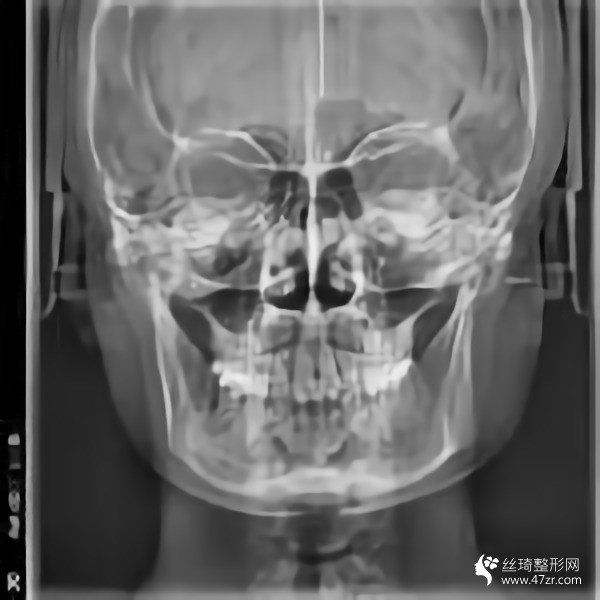

金柱翰院長(zhǎng)韓國(guó)頜面整形專家、韓國(guó)鼻整形專家、下頜角截骨術(shù)技術(shù)專家、韓國(guó)“微整形技術(shù)研究”專家,多次接受記者采訪,南京醫(yī)科大學(xué)國(guó)際整形教學(xué)研究中心副主任,南京醫(yī)科大學(xué)友誼整形醫(yī)院專家委員會(huì)常委;擅長(zhǎng)鼻整形手術(shù):自體鼻中隔軟骨移植隆鼻,耳軟骨移植隆鼻,肋骨移植隆鼻,假體隆鼻,鼻尖鼻翼整形手術(shù),各種畸形鼻的矯正,隆鼻失敗的修復(fù),歪鼻的矯正;

從高中開始,人們就一直說我的臉很方。就算不直接說臉,我也會(huì)說臉很大。每次聽到心里都很無(wú)奈,臉上都在埋怨我...每次我回嘴的時(shí)候,也是一副滿不在乎的表情。然而,我的心還是不自覺地開始關(guān)心它。說白了,我要小一點(diǎn)的臉。其實(shí)我一直有做下頜角的想法。之前我還在讀書,沒錢?,F(xiàn)在出來(lái)工作了,經(jīng)濟(jì)獨(dú)立了,咨詢了醫(yī)院說可以,終于可以解決這個(gè)大面子問題了

手術(shù)后15天。過來(lái)拆線。反正我覺得我更喜歡自己。一點(diǎn)都好看??雌饋?lái)很可愛。目前有點(diǎn)腫,但輪廓線條開始慢慢顯現(xiàn)。畢竟拆線?;謴?fù)狀態(tài)還是很滿意的。目前較重要的是照顧好自己。父母不在身邊。我還沒有過恢復(fù)期。我不能吃得太隨便。我必須注意我的飲食。這個(gè)真的是先苦后甜。不過為了后面的恢復(fù)果,一切都是值得的

回來(lái)快一個(gè)月了,基本沒有腫脹,輪廓清晰柔和。不知道是不是錯(cuò)覺,感覺皮膚細(xì)膩多了。哈哈,雖然有美顏加持,但是大家看不出來(lái)很正常,但是可以自己感受一下。院長(zhǎng)的技術(shù)真的很好,不愧是變臉王。剛來(lái)的時(shí)候看到幾個(gè)美女好像是花錢磨骨頭的,表現(xiàn)的多火啊。合格的醫(yī)生就是不一樣,讓人安心。醫(yī)院里的人手術(shù)后一直在回來(lái)康復(fù)。說起來(lái)有點(diǎn)太熱情了,讓我不敢接電話。

我又來(lái)了。我不記得上次是多久了。年紀(jì)大了記憶力下降了很多,但身邊認(rèn)識(shí)的很多人也會(huì)這樣。好像沒有明X的辦法。再說說我的下頜角手術(shù)。雖然手術(shù)的時(shí)候感覺不深,但是手術(shù)后確實(shí)記得很深,總是需要經(jīng)歷一些徹骨的寒冷,梅花才會(huì)有香味。較近的照片給你們發(fā)一波,如果手術(shù)做的好那么你以后就不會(huì)后悔了。

在生活中,我們往往忘記了健康和鍛煉,大多數(shù)人會(huì)在自己的世界里沉默,但生活中的許多實(shí)際問題仍然會(huì)把你拉回現(xiàn)實(shí)。我其實(shí)很喜歡去健身房,但是是時(shí)間問題導(dǎo)致我沒能得到我想要的。另外,我在下頜角休息了很久,臉部好了很多,運(yùn)動(dòng)還是不可或缺的。其實(shí)我覺得健康較重要,其次是外表和對(duì)自己的信任,哈哈